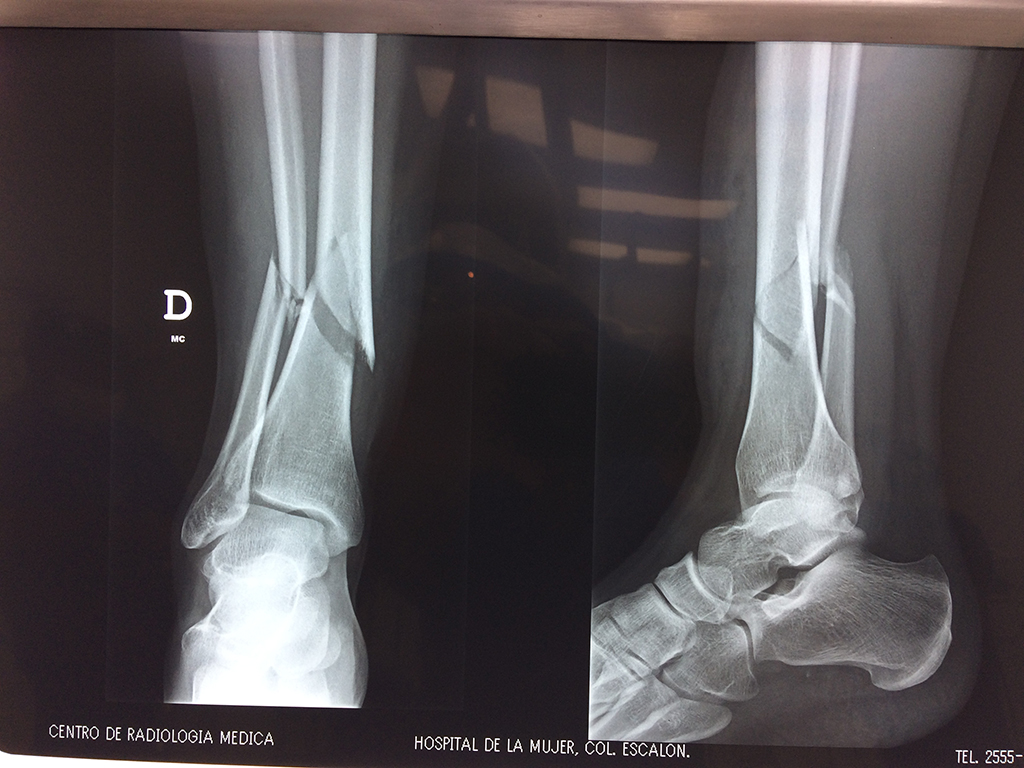

Cirugias en El Salvador - Perone y Tibia

Aunque cada uno de estos huesos puede fracturarse por separado, normalmente la rotura es una lesión que se produce de forma conjunta

La mayor parte de las roturas implican a la parte proximal del hueso (parte del hueso próximo a la rodilla) o a la parte distal (parte del hueso cerca del tobillo).

Debido a la fina cobertura de piel que recubre la tibia y el peroné, las fracturas generalmente son abiertas, es decir, el hueso roto rasga la piel, atravesándola. Las fracturas de tibia y peroné generalmente se producen por un fuerte impacto o torsión.